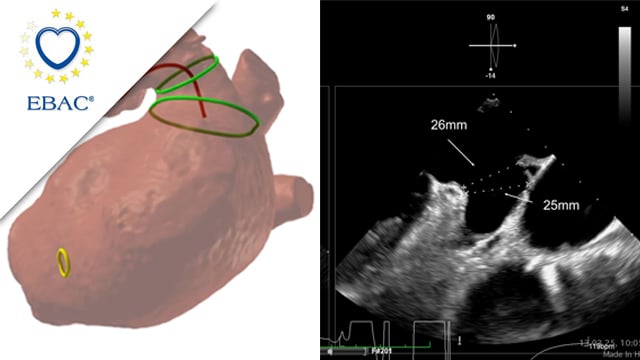

Severe MR in a high-risk patient with a suboptimal anatomy for M-TEER: what other options can we find?

Multimodality imaging reveals fibro-calcific leaflet disease, restricted motion, and a short posterior leaflet, making him a suboptimal candidate for M-TEER and prompting consideration of transcatheter mitral valve replacement. How would you treat?